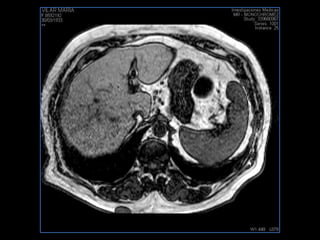

PROTOCOLO abdomen COR T2, AXIAL supresion grasa AX T1 +SAG T2  CON   GADOLINIO :  COR T1+AX T1(DIN) SAT: NO  FASE: RL THK: 6MM  COIL:  GAP: (FACTOR 1.4) 2MM FOV: 40 CM NEX:2 SINCRONIZACION RESPIRATORIA EN 3 O 4 CICLOS ALE